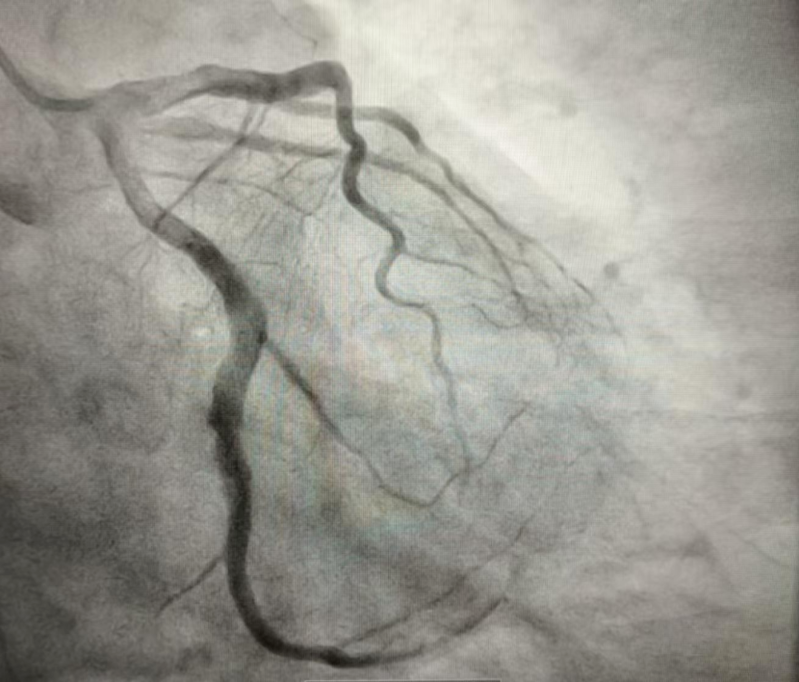

2024年10月的某天,患者程某某因胸悶兩天,前來惠州市中心人民醫(yī)院博羅分院(博羅縣人民醫(yī)院)心血管內(nèi)科就診。經(jīng)診查,診斷為冠心病、急性非ST段抬高型心肌梗死 KillipI級,GRACE評分122分,危險分層高危。行冠脈造影示回旋支遠段近端見大量血栓影、狹窄90%,遠段遠端見大量血栓影、狹窄100%閉塞,前向血流TIMI0級(圖1)。心血管內(nèi)科團隊予為患者行PTCA和血栓抽吸術,復查造影顯示:回旋支遠段近端血栓無變化,遠段遠端血栓消失(圖2)。考慮血栓負荷重,回旋支遠段近端暫不宜行支架置入術,擬給予抗栓治療后擇期復查冠脈造影。

文章配圖

(圖2)